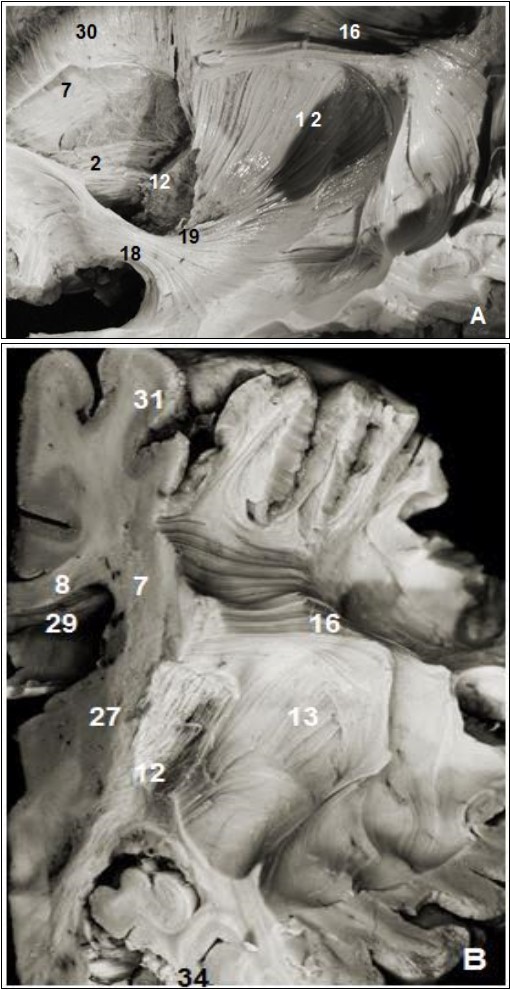

Figure 4.(A) Lateral view of left cerebral hemisphere after dissection and (B) coronal view. 2. Anterior thalamic radiation, 7. Subependymal stratum, 8. Corpus callosum, 12. Internal capsule, 13. External capsule, 13. SLF, 15. Corona radiata, 16. Uncinate fasciculus, 19. Inferior frontal occipital fasciculus, 27. Putamen, 28. Globus pallidus, 29. lateral ventricle, 31. Parietal pole, 34. Temporal pole.